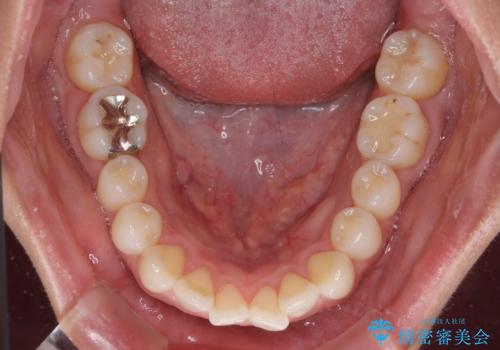

- くちばしのような前歯の突出感を気にして来院された患者様です。

上下左右第一小臼歯4本を抜歯して、積極的に口元を引っ込めるよう、ワイヤー装置にて矯正治療を行うこととしました。

抜歯矯正を行ったことで、顎先のつっぱり感や口元の閉じにくさを解消することができました。